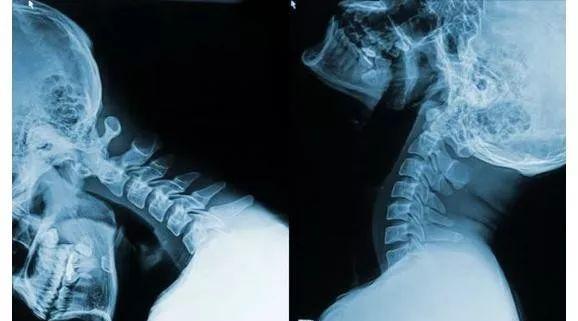

颈椎病是人们比较常见的疾病,颈椎病会引起颈肩疼痛,并且还会伴有头晕乏力的现象,颈椎病不仅会导致生活质量下降,还会出现多种健康问题。

颈椎病发病率高的原因:

1、长时间坐在办公室看书

长时间保持头颈单一姿势、长时间坐在办公室看书的人易患颈椎病。

2、姿势不好

例如,躺在床上看电视、读书、睡在高枕头、坐在床上等;睡在卧铺车里,睡觉时,肌肉保护差,制动时容易发生颈部损伤。

3、颈椎结构发育不良

先天性小椎管也是发病的基础。中枢椎管和神经根管的颈椎病发病率是正常人的1倍。

颈椎病在生活上带给我们哪些危害:

1、睡眠障碍,颈椎病患病部位有剧烈的疼痛感,睡觉的时候疼痛更是难以忍受,一整晚根本睡不着。

2、引起高血压,颈椎病患者大部分都会有胸闷、气短的情况出现,致使心跳加速,诱发高血压,所以患者经常感到头晕。

3、导致瘫痪,颈椎病患者脖子周围韧带松弛,无法维护关节的稳定性,容易发生错位,影响周围的骨神经,一旦受伤就会患上瘫痪。